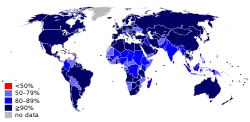

По современным представлениям, для полного искоренения кори в стране уровень охвата вакциной в каждом из её районов должен быть не менее 95 %[15].

Охват двумя дозами вакцины от кори в России соответствует рекомендованному ВОЗ уровню (свыше 95 %) начиная с 2003 года[52].

На 2009 год было отмечено, что для полного искоренения кори в стране уровень иммунизации должен превышать 93—95 %, для чего уровень охвата двумя дозами вакцины в каждом из её районов должен быть не менее 95 %; а для снижения смертности от кори, охват двумя дозами вакцины должен превышать 90 % на национальном уровне и 80 % в каждом районе страны[15].

В 2010 году были поставлены новые цели: к 2015 году увеличить охват детей в возрасте 1 года первой дозой вакцины до 90 % на национальном уровне; поддерживать ежегодную заболеваемость корью на уровне менее 5 случаев на миллион; и сократить оценочную смертность от кори по сравнению с оценкой 2000 года на 95 %[4].

Ускорение в 2000-х годах мероприятий по иммунизации от кори, предпринятое ВОЗ, и повышение охвата с 72 % в 2000 году до 84—86 % в 2010—2017 годax, оказало значительное воздействие на снижение заболеваемости и смертности от кори, однако поставленные цели (90 %, затем 95 % снижение смертности) не были достигнута ни к 2010 году, ни к 2015 году. Глобальная смертность от кори с 2000 до 2017 годы снизилась на 80 %, смертность за эти годы оценивалась в 545 000 случаев (первоначально, 1 000 000 случаев[60]) и 111 000 случаев, соответственно[4][61]. Количество учтенных случаев кори снизилось от 700—870 тысяч в 1996—2000 годах до 212—360 тысяч случаев с 2011—2015 годах[62]. На 2016 год, корь считалась причиной 1,3 % детской смертности[6]

С 2004 года количество стран, где достигнут действительно высокий охват вакцинацией от кори практически неизменно, и составляет около 80 стран с охватом первой дозой в 95 % и выше и 45—50 стран с охватом двумя дозами вакцины в 95 % и выше.

Эксперты ВОЗ отмечают, что причиной сложившейся ситуации стало резкое снижение уровней вакцинации[уточнить] против кори, особенно в маргинальных группах населения в ряде стран Европы; в Евросоюзе только в четырёх странах достигнут рекомендуемый охват двумя дозами вакцины от кори (свыше 95 %), в то же время накануне вспышки заболеваний в европейском регионе был достигнут рекордно высокий (90 %) охват второй дозой противокоревой вакцины и увеличился (до 95 %) охват первой дозой[69][67][65]. За предыдущие годы (2000—2017) уровень охвата первой дозой вакцины от кори на Украине сильно падал в период 2009—2016 годов, когда он не достигал 80 %, в то же время в США, России, Бразилии этот показатель существенно не менялся, составляя, по оценкам ВОЗ, 90—93 %, 97—99 %, и 95—100 %, соответственно. ВОЗ назвала недоверие к вакцинации одной из 10 главных угроз здравоохранению в 2019 году[70].